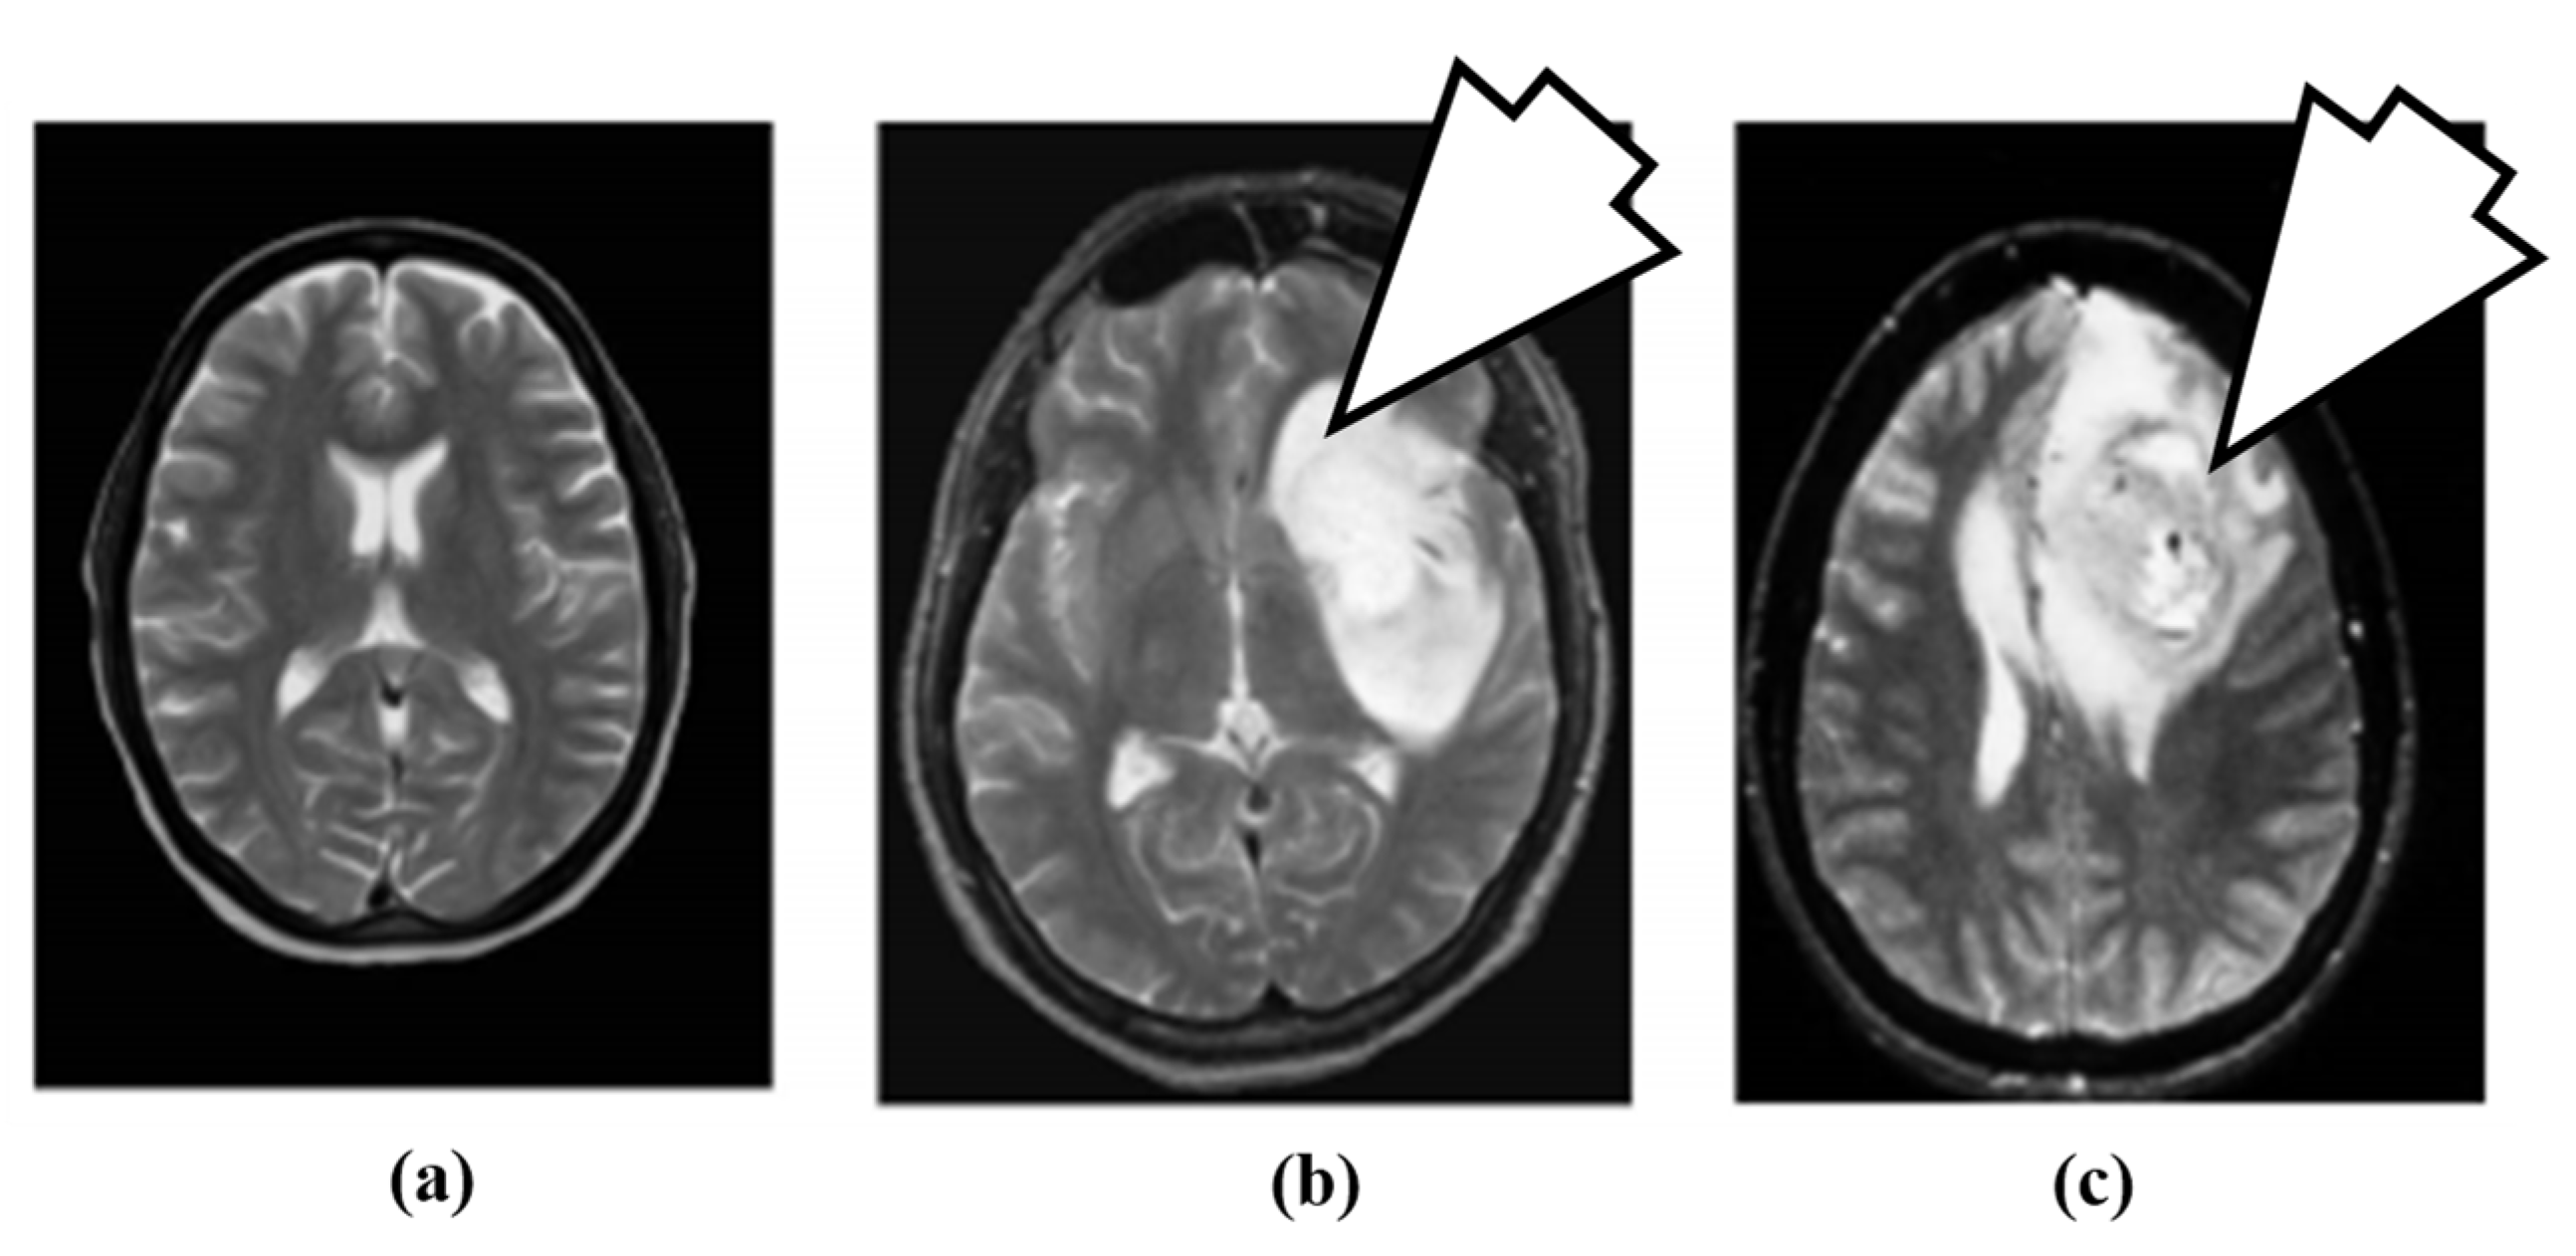

3.2. Magnetic Resonance Imaging

5.3. Imaging Test